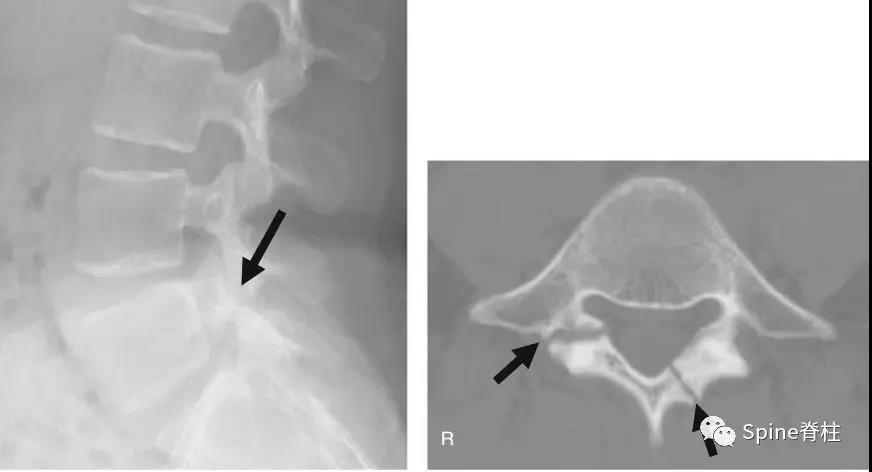

椎弓根钉准确性的CT评价方法主要有如下几种。置钉失败可造成灾难性的后果,估计大家都听过坊间传闻:那个医院钉子打穿了主动脉,那个大腕钉子打瘫了脊髓。打瘫了基本上麻醉醒了就知道了,很少发生钉子碰到脊髓慢慢发生神经症状的情况。